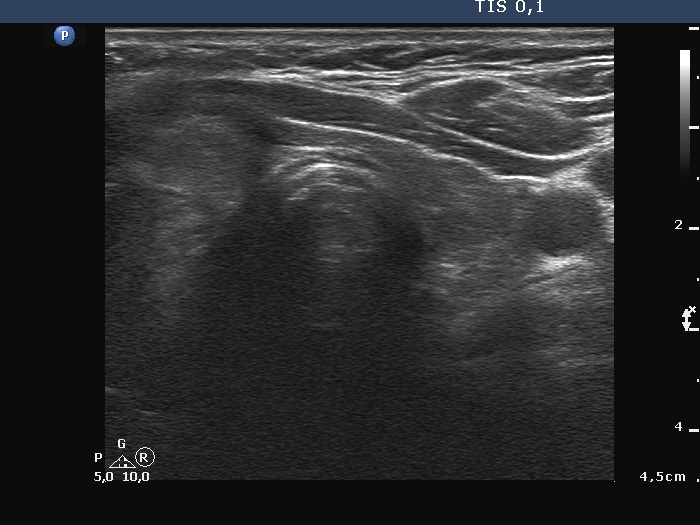

First examination (first row of images):

Ultrasonography. The thyroid was hypoechoic. There was a large, irregular, echonormal mass in the right lobe. The lesion presented both intranodular and perinodular vascularity. The left lobe was decreased in size.